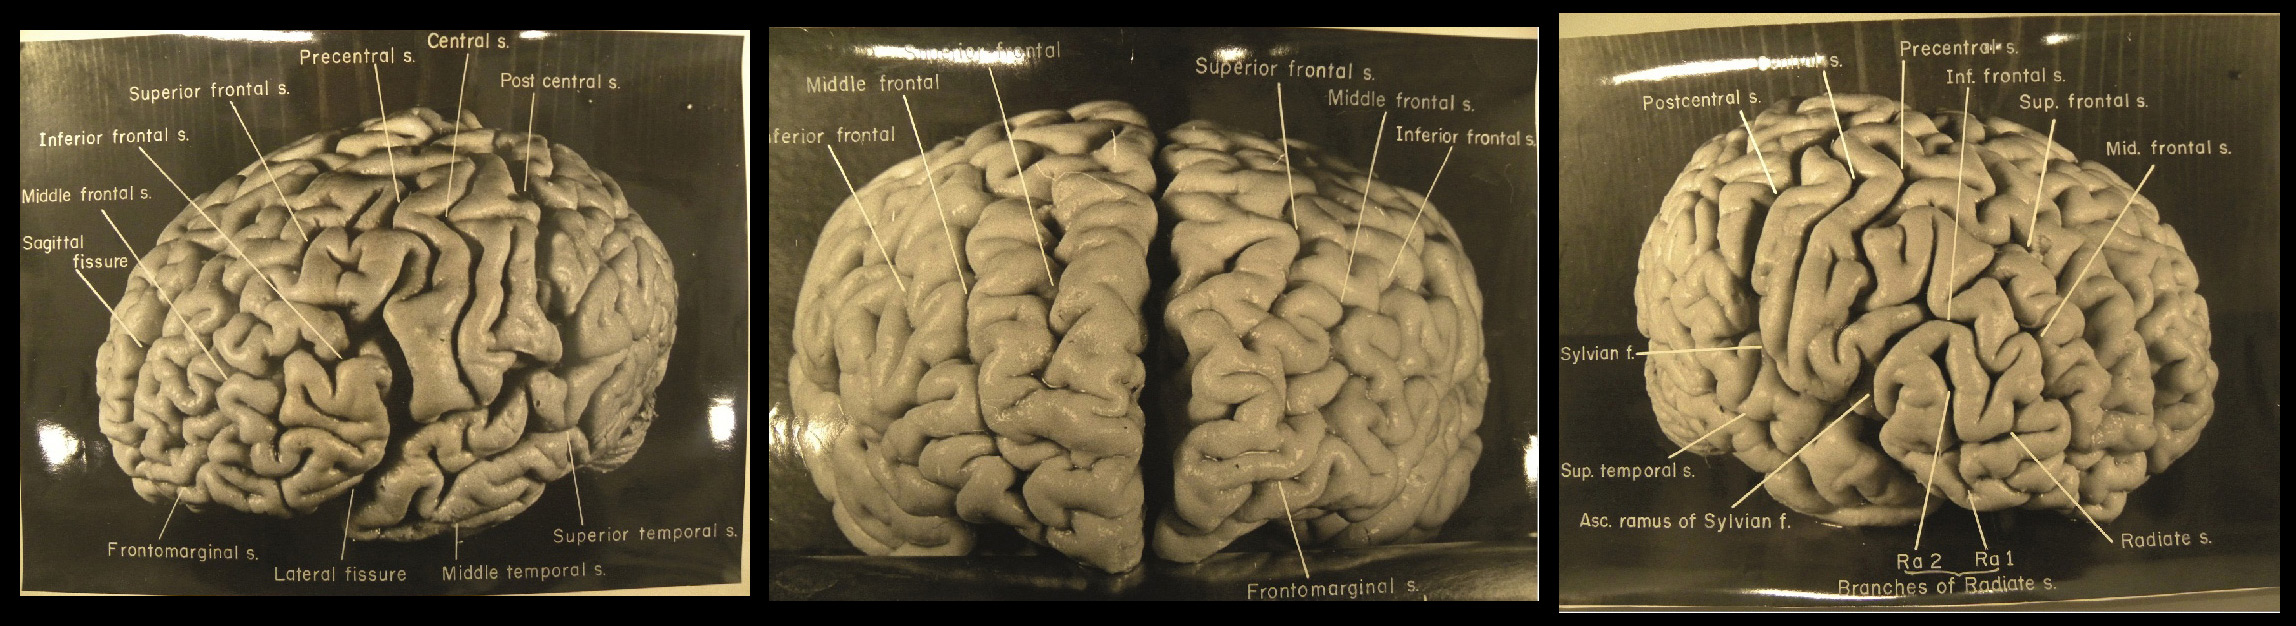

Https www alamy com a specimen of nobel physicist albert einsteins brain is seen in a glass slide at an exhibition at the wellcome collection in london march 27 2012 weve pickled it dessicated it drilled it mummified it chopped it and sliced it over centuries yet as the most complex entity in the known universe the human brain remains a mysterious fascination with samples of albert einsteins preserved brain on slides and specimens from other famous and infamous heads such as the english mathematician charles babbage and notorious mass murderer william burke an exhibition opening in london this week image377121679 html (Dateityp jpg)

Einsteins Brain High Resolution Stock Photography And Images Alamy